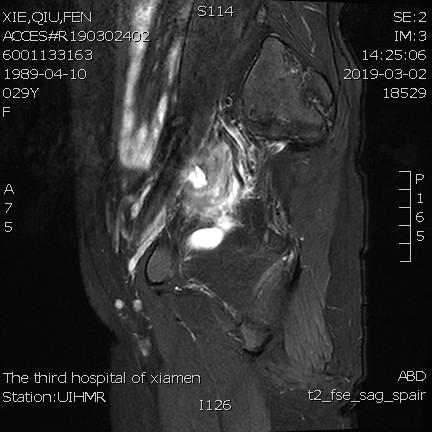

- 术前MRI显示子宫明显增大,病灶主要位于子宫前壁

术前MRI显示子宫明显增大,病灶主要位于子宫前壁